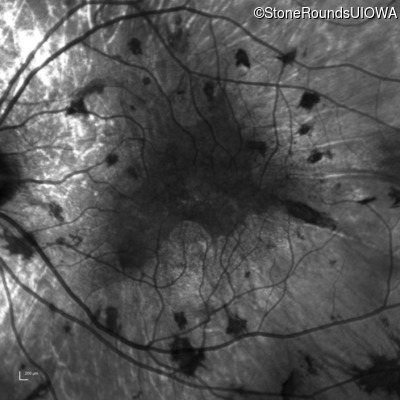

Infrared Fundus Photograph - Right - 20/25 +1

Exemplar